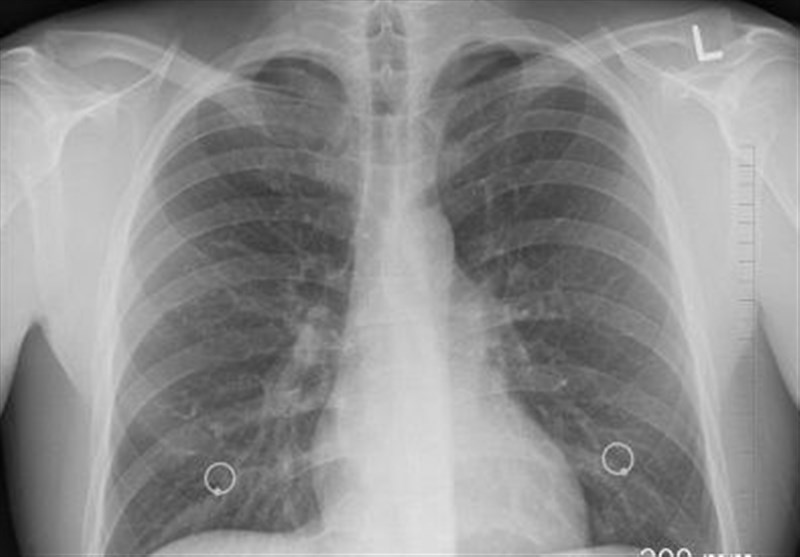

وی عنوان کرد: سرطان ریه یکی از پنج سرطان کشنده در جهان است. به دلیل تهاجمی بودن، زمان کمی برای درمان باقی میگذارد و متاسفانه بسیاری از بیماران در سالهای اول فوت میکنند. میزان ابتلا در بخش مردان حدود 12.7 در هر صد هزار نفر و در میان زنان رقمی کمتر از مردان است. در استان گلستان اما میزان شیوع این بیماری بالاتر است و در مردان میزان ابتلا 21.3 در هر صد هزار نفر (بسیار بالاتر از میانگین کشوری) و در میان زنان 5.21 در هر صد هزار نفر است.

روشندل با اشاره به عوامل خطر شناخته شده سرطان ریه گفت: مصرف سیگار (ریسک بسیار بالا)، در معرض دود سیگار بودن، مصرف الکل و نوشیدنیهای الکلی، مواجهه شغلی با تشعشعات (مثل برخی محیطهای بیمارستانی یا صنعتی)، آلودگی هوا و آب، تریاک (به عنوان یک عامل خطر مهم و خاص در کشور) است.

معاون تحقیقات و فناوری دانشگاه گلستان با اشاره به نتایج یکی از پژوهشها در زمینه سرطان گفت: این پژوهش با همکاری انستیتو سرطان دانشگاه علوم پزشکی تهران و به صورت مطالعه مورد- شاهدی چندمرکزی انجام شده است که مطالعه روی 627 بیمار مبتلا به سرطان ریه از 10 استان کشور انجام شد.

وی خاطرنشان کرد: مصرف منظم تریاک، خطر ابتلا به سرطان ریه را 3.6 برابر افزایش میدهد و در صورت مصرف همزمان تریاک و سیگار، خطر ابتلا به 13 برابر میرسد. افرادی که دو بار یا بیشتر در روز تریاک مصرف میکنند، 9 برابر بیشتر در معرض خطر هستند.

روشندل با اشاره به اینکه تریاک دارو نیست و یک ماده سرطانزاست، بیان کرد: این پژوهش نشان داد که اثر مخرب تریاک در زنان بارزتر است و خطر ابتلا در آنها 7 برابر افزایش مییابد. خطر آن به تنهایی بسیار بالاست و مصرف مشترک با سیگار، خطر را به طور نجومی افزایش میدهد.